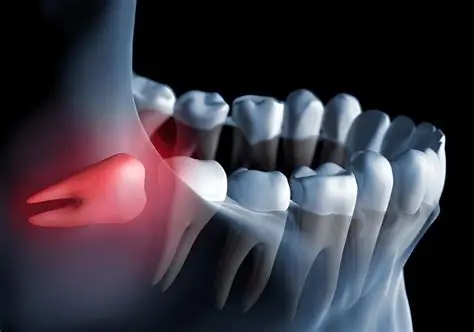

Urgência odontológica 24h em Campos do Jordão

Atendimento mais ágil para dor, trauma, fratura, inchaço e outras intercorrências.

Contato mais rápido para dor, trauma, fratura, inchaço e intercorrências que exigem atenção imediata.

Sim. Dor intensa, trauma, fratura, inchaço e outras intercorrências podem ser direcionadas com mais rapidez pelo WhatsApp.